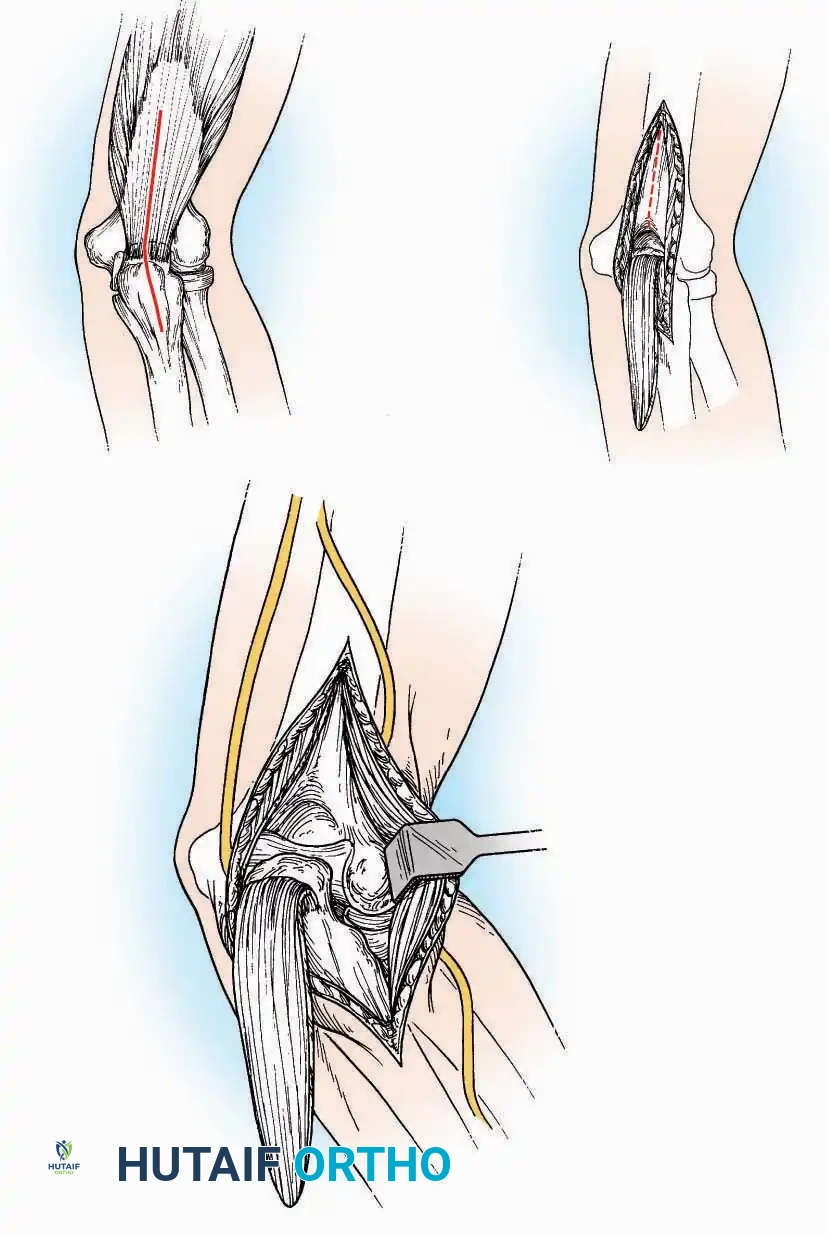

Anterior Approach

Indications: Total ankle arthroplasty (TAA), anterior ankle arthrodesis, and excision of anterior tibial/talar osteophytes (anterior impingement).

💡 Clinical Pearl

Gaining access to the medial gutter (the articulation between the medial malleolus and the medial articular facet of the talus) can be challenging through a pure anterior approach. Meticulous medial subperiosteal dissection of the joint capsule is required to avoid excessive traction on the anterior neurovascular bundle.

Surgical Technique:

* Incision: Make a 10 to 15 cm longitudinal incision over the anterior aspect of the ankle, centered exactly midway between the medial and lateral malleoli.

* Superficial Dissection: Incise the superficial fascia. Identify and protect the superficial peroneal nerve branches laterally and the saphenous nerve medially.

* Internervous Plane: The deep dissection exploits the plane between the Extensor Hallucis Longus (EHL) tendon (innervated by the deep peroneal nerve) and the Extensor Digitorum Longus (EDL) tendons (also innervated by the deep peroneal nerve).

* Neurovascular Bundle: Incise the extensor retinaculum. Carefully identify the anterior tibial artery and the deep peroneal nerve, which typically lie between the EHL and EDL, or directly deep to the EHL. Retract the neurovascular bundle laterally with the EDL, or medially with the EHL, depending on the specific anatomical variant encountered (lateral retraction is most common).

* Capsulotomy: Incise the anterior joint capsule longitudinally. Elevate the capsule subperiosteally from the anterior tibia and the talar neck to expose the entire tibiotalar articulation.